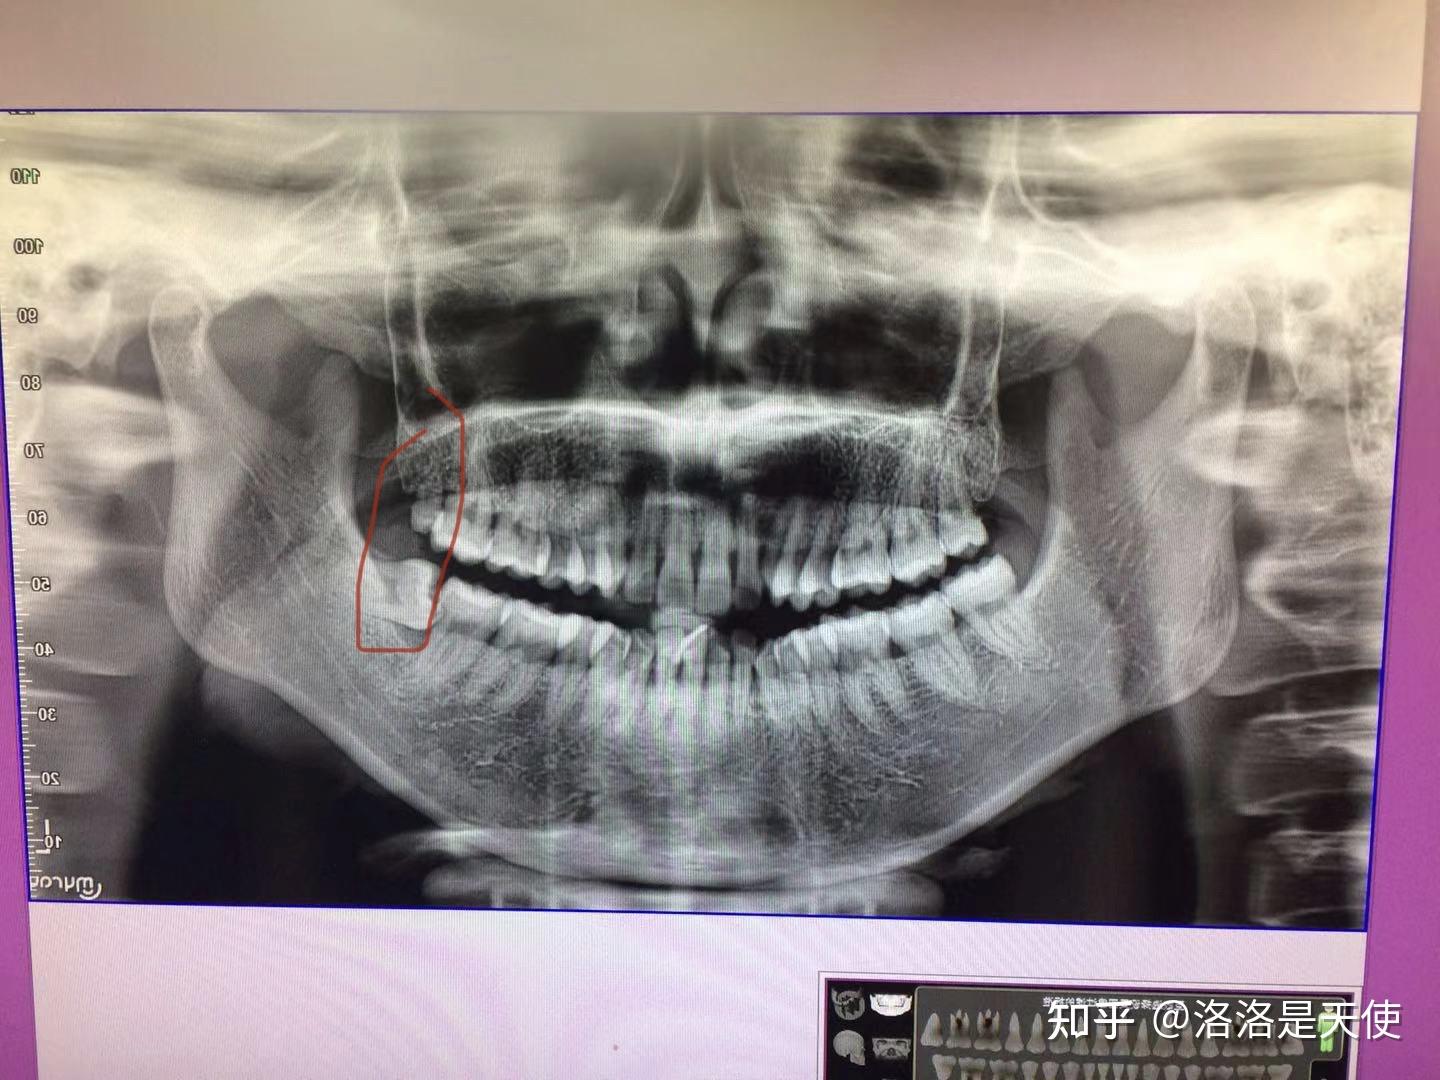

全景片上牙根在神经管里的水平阻生智齿的微创拨除

我这颗横着的智齿,大夫说不用拔,说我年龄大了,也不会再长了,但我怕顶